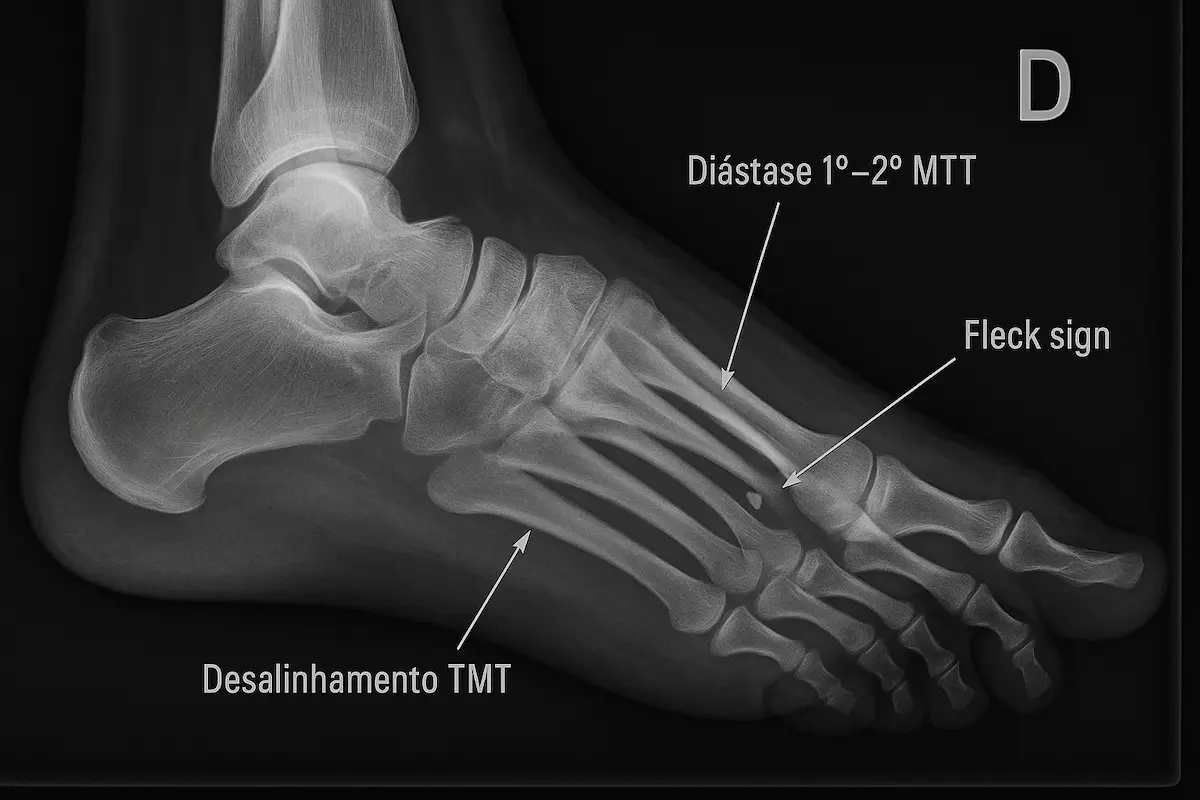

Começa pela história clínica e exame físico detalhado (testes da gaveta anterior, inversão e eversão, rotação externa e compressão da sindesmose).

- Radiografias: incluem incidências com estresse para flagrar subluxação.